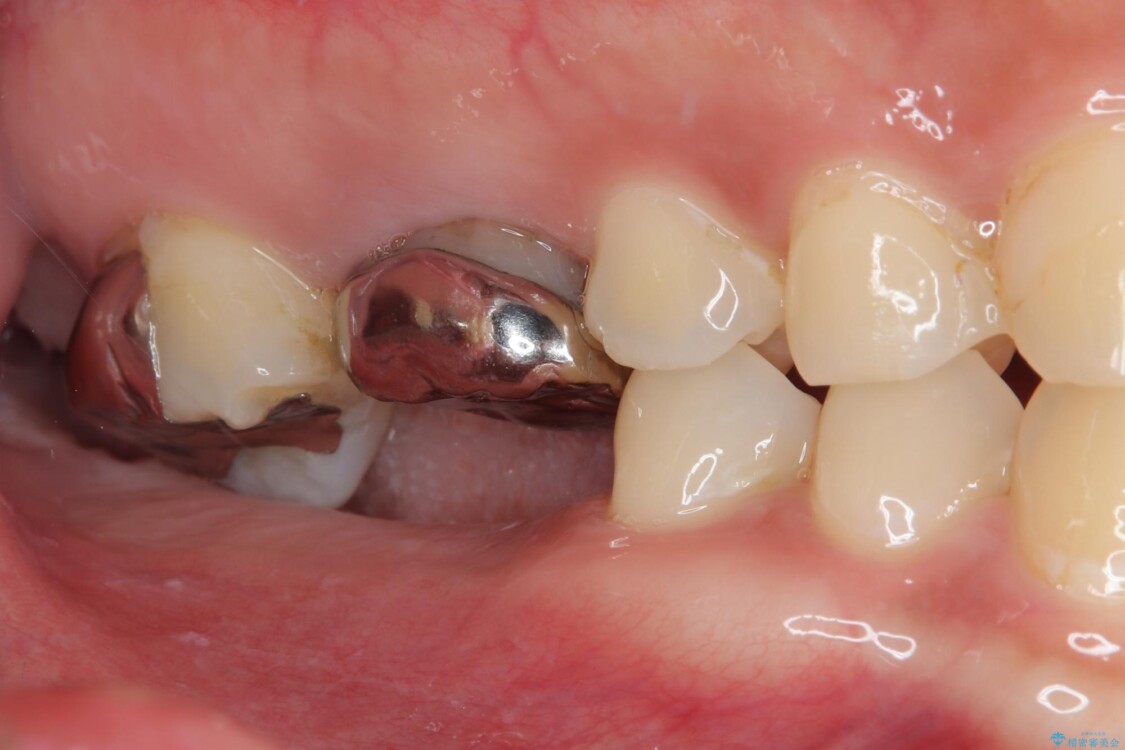

スペースが整った段階で、右下の第一大臼歯と第二大臼歯にインプラントを埋入。

その後、挺出していた右上第一大臼歯と第二大臼歯に装着されていた銀歯についても、審美性と適合性の向上を目的に、オールセラミッククラウンにやり替えました。

これにより、より自然で美しい見た目と、高い精度の咬合が得られています。

• 挺出歯を圧下してスペースを確保!目立たない部分矯正で下顎大臼歯にインプラント治療を実現 治療後画像